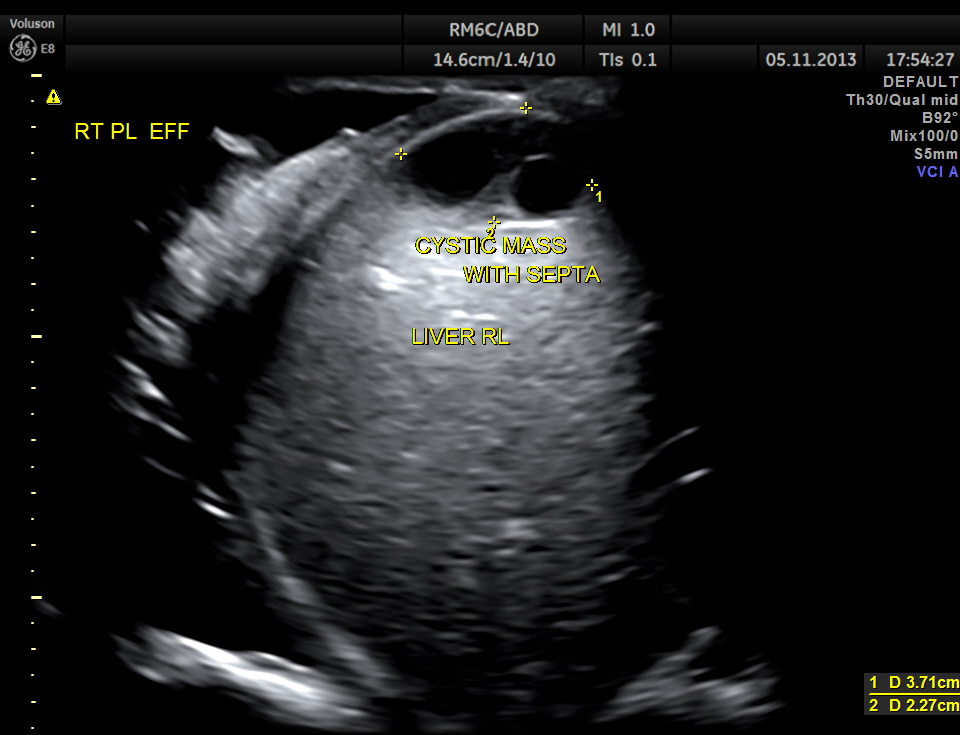

Septated cystic mass seen in the free surface of the right lobe of the liver.

This patient had a painful metastatic nodule in the right lobe of the liver. He also had loculated sub diaphragmatic collection and a septated cystic mass in the free surface of the liver.